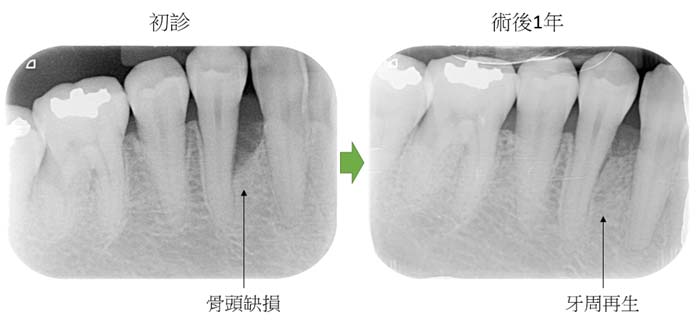

牙周再生手術治療案例1